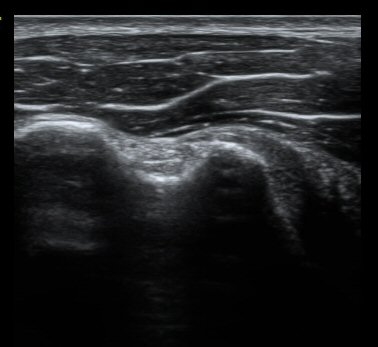

°üÂûµÊ(±×¸² 3, 4). °ß°©ÇÏ±Ù°Ç È¾´Ü¸é°Ë»ç¿¡¼­µµ °ß°©Çϱٰdz» °£±ØÀÌ °üÂûµÊ(±×¸² 5).

±Ø»ó°Ç Á¾´Ü¸é°Ë»ç¿Í Ⱦ´Ü¸é°Ë»ç¿¡¼­ ±Ø»ó°Ç³» ¹Ì¼¼ÇÑ °£±ØÀÌ °üÂûµÊ(±×¸² 6, 7, 8).